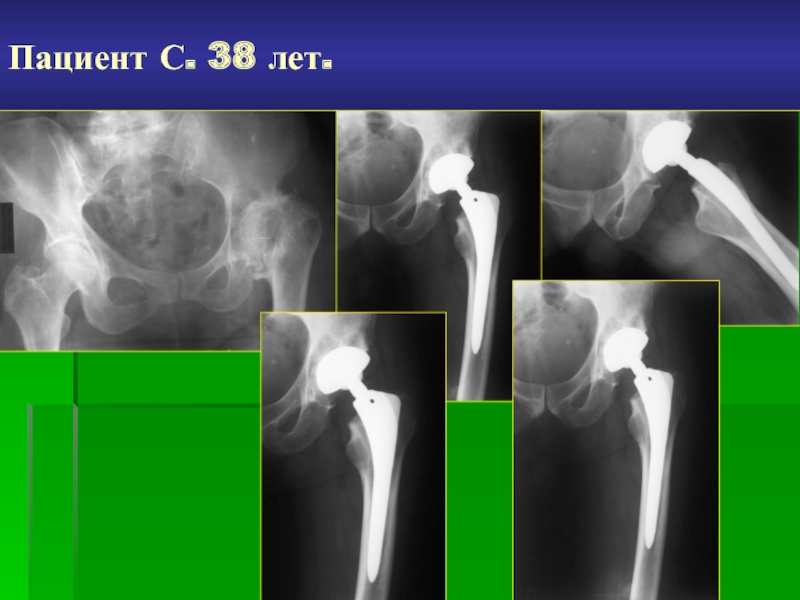

Слайд 30Пациент С. 38 лет.

Пациент С. 38 лет.